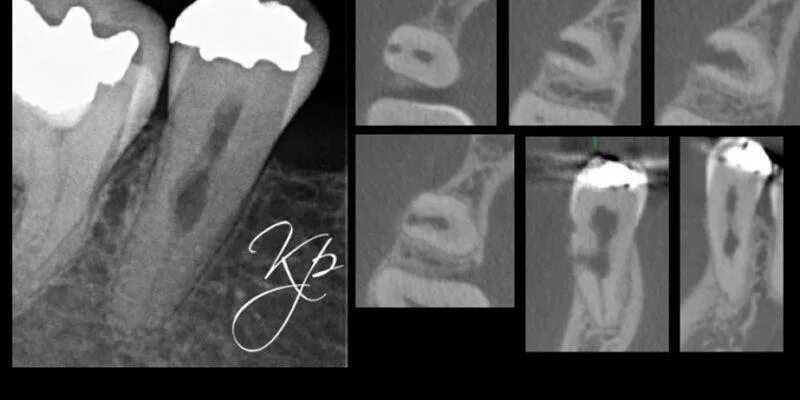

Признаки резорбции